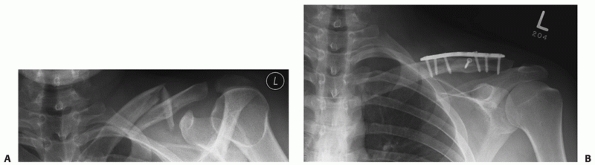

FIGURE 36-7 A “floating shoulder” injury. This patient was injured in a motor vehicle accident. A. Anteroposterior radiograph demonstrates a displaced, shortened left clavicle fracture. B. Computed tomography scan of the shoulder reveals a comminuted glenoid neck fracture. C. There is significant clinical deformity. D. Intraoperatively, the fracture is reduced with the aid of reduction clamps, and an anterior fixation plate is applied (E). Symmetry of the shoulder was restored by clavicle fixation alone (F), and it was not necessary to repair the glenoid fracture. G. There was an excellent clinical result with full restoration of motion and a Constant-Murley Shoulder Outcome Score of 95.